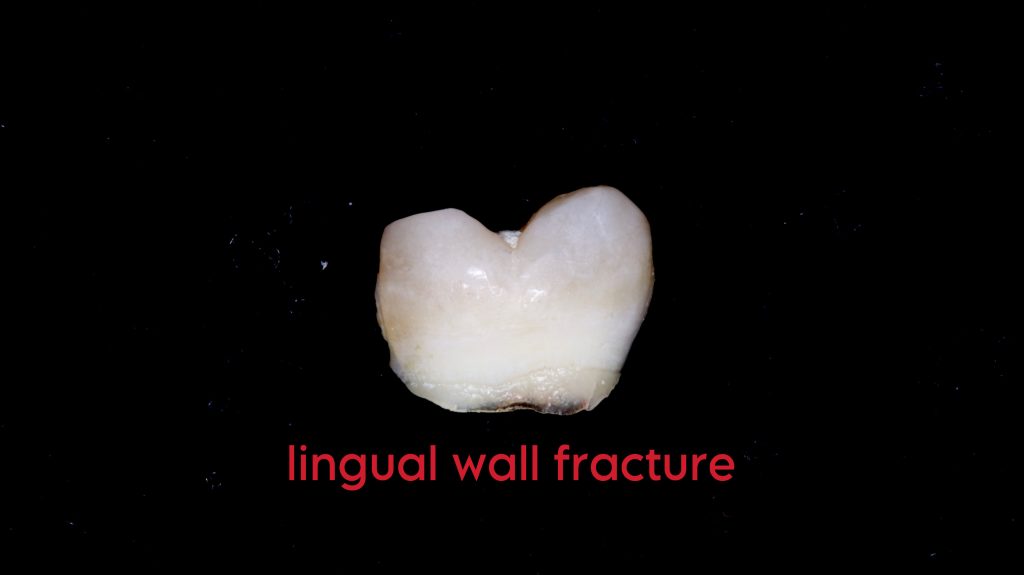

This picture shows lingual wall fracture of lower 6